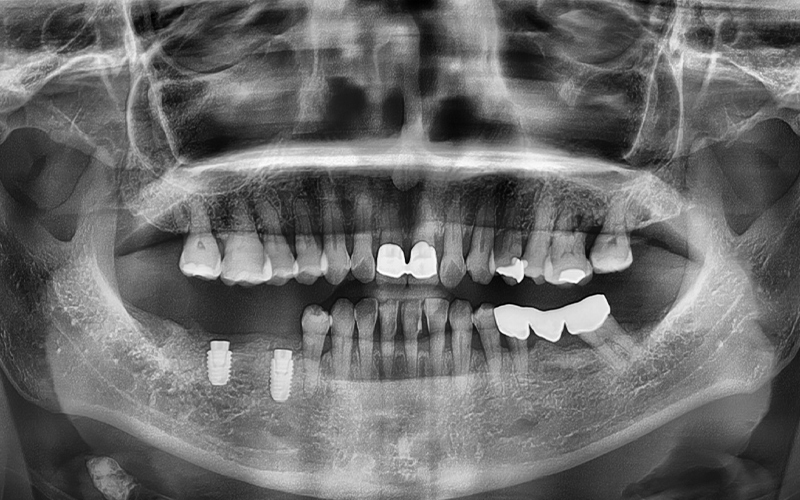

She was experiencing pain in the lower molars on both sides,

and we took a panoramic X-ray

to check the situation in detail.

🦷 Summary of the condition at the time of the visit

✔ The first lower molar on the right

had already been extracted

✔ The second lower molar on the right

was judged to be difficult to preserve due to tooth fracture,

so extraction was decided

✔ The second premolar had a crown already in place,

and it was part of a bridge connected

to the second lower molar

✔ The lower left wisdom tooth

needed extraction due to inflammation